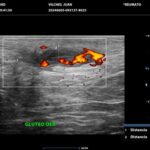

La HS es una enfermedad crónica, inflamatoria inmunomediada, sistémica, recurrente y debilitante de los folículos pilosos terminales con origen en las glándulas apocrinas de estos. Presenta habitualmente lesiones dolorosas, profundas e inflamadas, localizadas más frecuentemente en las regiones axilares, inguinales y anogenitales. El 80% de las lesiones tienen ubicación profunda de difícil acceso al examen físico. Su diagnóstico es clínico pero el ultrasonido (US) de alta resolución con Doppler es un método que cumple actualmente un rol esencial para establecer el diagnóstico, estadificar la enfermedad y detectar actividad, incluso en el caso de lesiones no pesquisadas en el examen físico. También nos permite monitorear el estado y la progresión de la HS, facilitando la evaluación rápida de distintos enfoques terapéuticos. Incluso, los cambios ecográficos pueden modificar la conducta terapéutica.

Los hallazgos ecográficos más relevantes son el ensanchamiento de folículos pilosos, engrosamiento y ecogenicidad anormal de la dermis, nódulos pseudoquísticos dérmicos, colecciones líquidas y tractos fistulosos. Por otro lado, el US nos permite valorar la localización exacta y extensión de las lesiones, su ecogenicidad, el grado de vascularización al examen Doppler y las eventuales complicaciones, e incluso la modificación de las lesiones en respuesta a la terapéutica instaurada. La HS se estadifica clínicamente mediante la clasificación de Hurley y los hallazgos ecográficos muestran correlación con cada estadio clínico.

El diagnóstico ecográfico resulta de importancia diagnóstica, tal es así que la ecografía de alta resolución y el estudio Doppler han ocupado un lugar preponderante en los últimos años. La ecografía de la piel permite identificar lesiones no encontradas en el examen físico, evaluando de manera fehaciente su extensión anatómica. El empleo de la ecografía en la HS es ideal, ya que el 80% de las lesiones ocurren en las capas más profundas y no en la superficie de la piel. Permite evaluar la localización exacta y extensión de las lesiones, su ecogenicidad, el grado de vascularización al examen Doppler, las eventuales complicaciones, e incluso la respuesta terapéutica.

El estudio ecográfico de alta resolución con Doppler tiene un rol fundamental en la categorización de las lesiones de HS en profundidad, incluso las subclínicas. Debemos incluir al US como técnica de elección para estadificar y monitorear pacientes con HS, ya que nos permite acceder a un diagnóstico rápido de lesiones típicas con las que podremos, en conjunto con la clínica, estadificar y seguir en el tiempo a los pacientes.